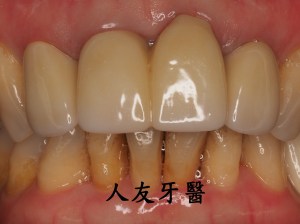

植牙後常見的問題,人工植牙雖然有著不會蛀的金屬質地,但它附屬的地基「齒槽骨」和周圍覆蓋的牙肉跟我們自己的牙齒一樣,植牙周圍若是清潔不乾淨,也會產生牙周病,造成「植體周圍炎」。

但尚未影響到硬組織,被稱為植體周圍黏膜炎;若已破壞到周遭骨頭,被稱為植體周圍炎。若周遭骨被破壞,最後可能造成植體失敗,需要移除,植牙等於做了白工。分析造成植體周圍疾病的原因,主要是細菌,如牙菌斑;咬合力量過大、牙套完成時殘留的黏著劑未清潔乾淨、製作不當的牙套也會。

植體周圍炎牙齒從外表看不出來,需從x光片才能看出來,為避免造成植體周圍組織發炎,甚至破壞到周遭骨頭,平時應注重牙齒清潔保養,選擇刷毛軟的牙刷清潔 , 搭配牙間刷去清潔牙縫 , 並定期回診檢查,確保牙齒健康。